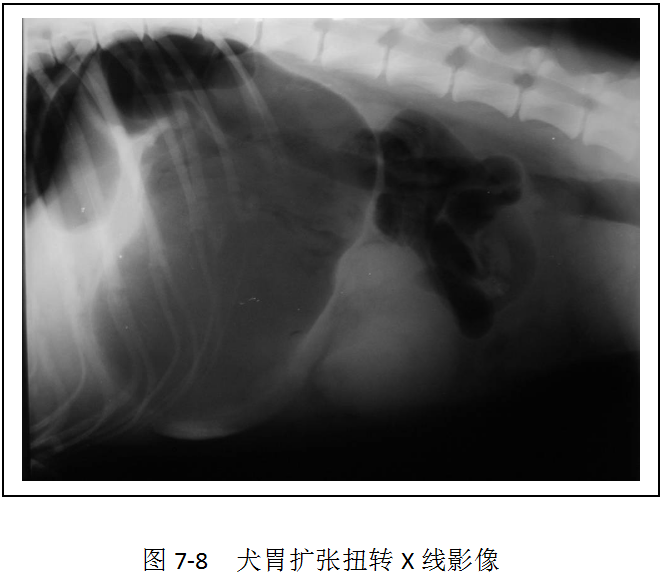

【拓展知识】腹部异常X线影像